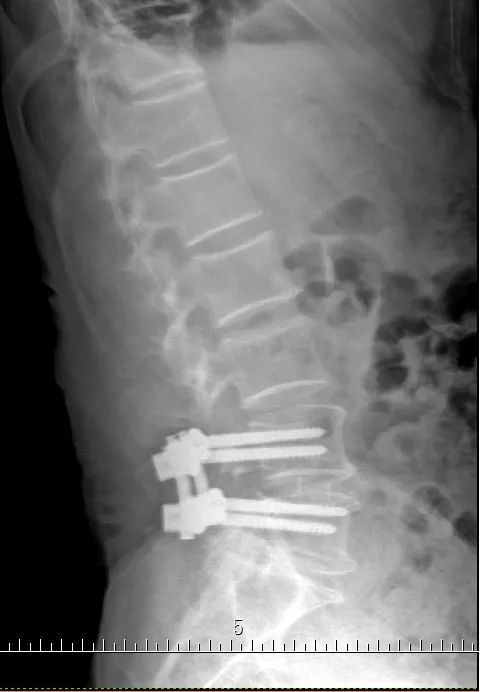

术后X光片

考虑到老伯已是82岁高龄,医院为他实施了经椎间孔入路的微创腰4/5椎管减压、椎间盘摘除,植骨融合内固定手术(mis-TLIF)。手术过程非常顺利,术中仅有少量的出血。术后第二天老伯就能自主翻身,第三天在腰围的保护和家人的协助下,就能缓慢起坐。术后第五天,老伯就开始在医护人员的协助下下地行走了。原先的腿痛几乎完全消失,走路时腰也挺直了。